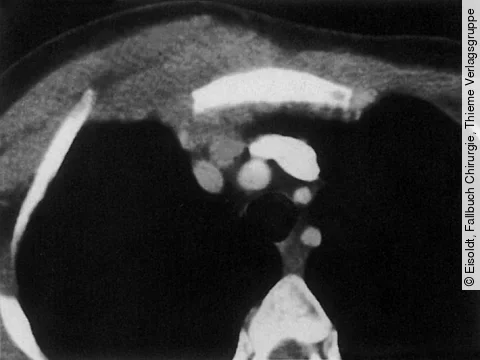

Die 59-jährige Patientin gibt an, zunehmende Atembeschwerden zu haben. Sie weiß von einer Asthma-Erkrankung, die seit vielen Jahren therapiert wird, und ist Nichtraucherin.